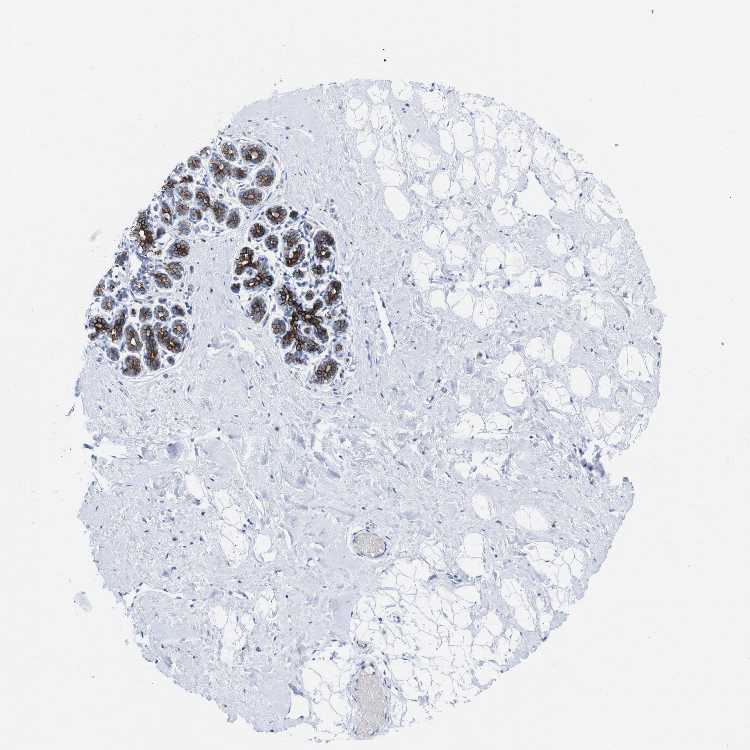

BREAST - Antibody stainingi

Antibody staining in the annotated cell types in the current human tissue is reported as not detected, low, medium, or high, based on conventional immunohistochemistry profiling in selected tissues. This score is based on the combination of the staining intensity and fraction of stained cells.

Each image is clickable and will lead to virtual microscopy that enables deeper exploration of all samples and also displays staining intensity scores, fraction scores and subcellular localization as well as patient and tissue information for each sample.

Antibody CAB013093

Adipocytes Not detected

Glandular cells High

Myoepithelial cells Not detected